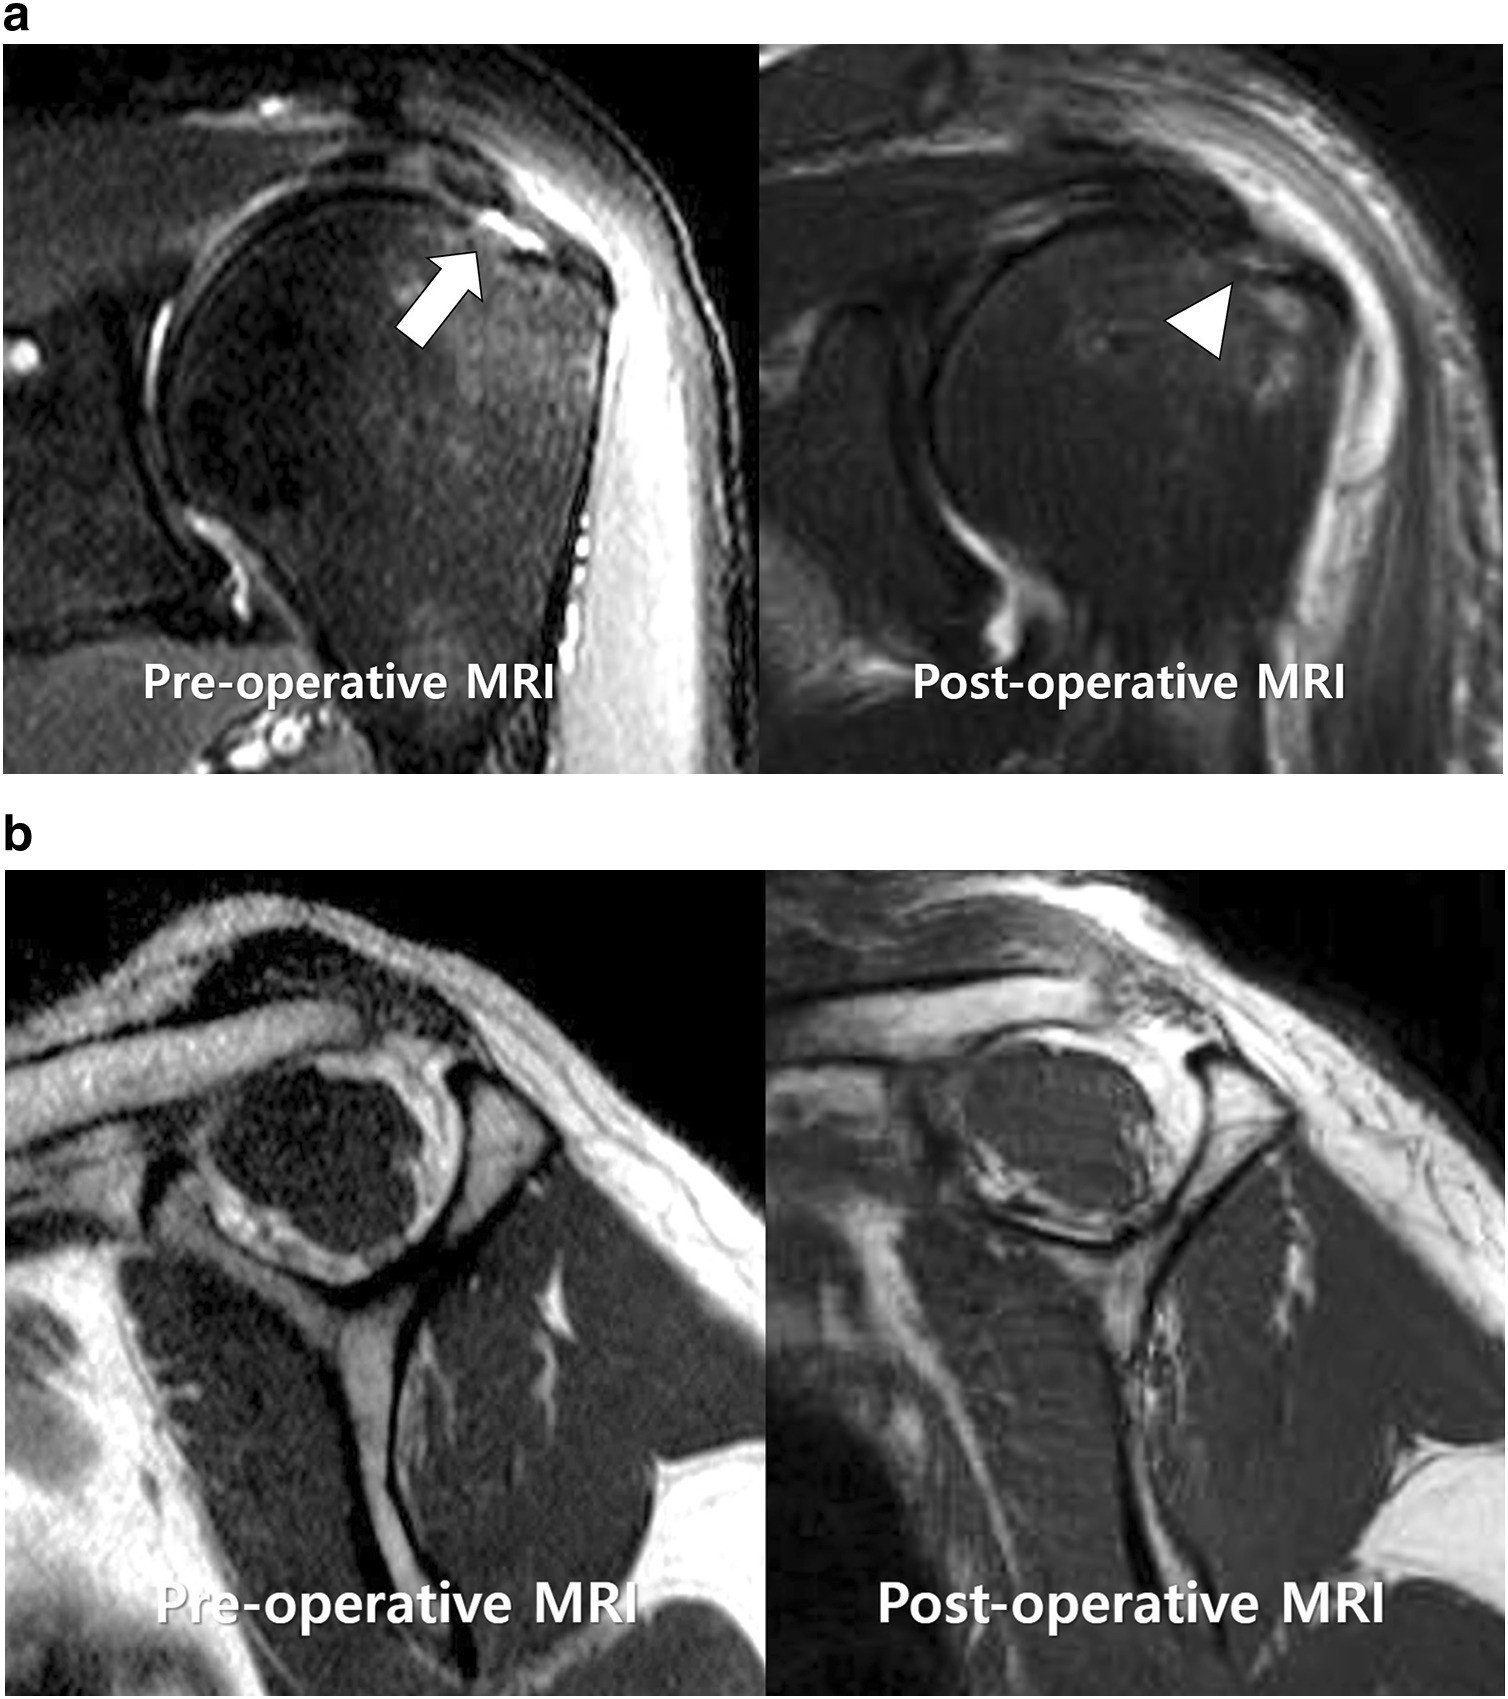

Articular Side

Articular Side : One is bursal and the other is articular.